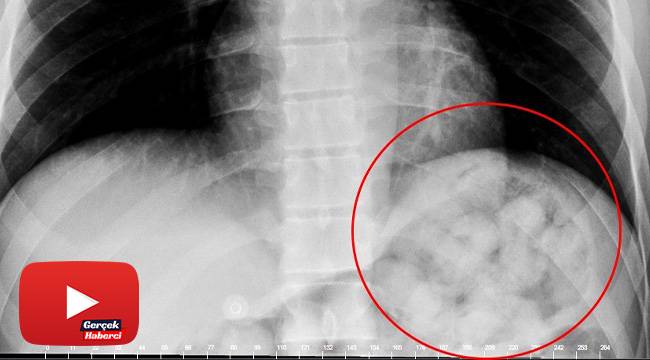

Karnından uyuşturucu zulası çıktı

Van’dan otobüsle Ankara’ya gelen yabancı uyruklu şahıs, yuttuğu 72 kapsül metamfetamin kapsülünün midesinde patlaması üzerine rahatsızlanarak hastaneye kaldırıldı.